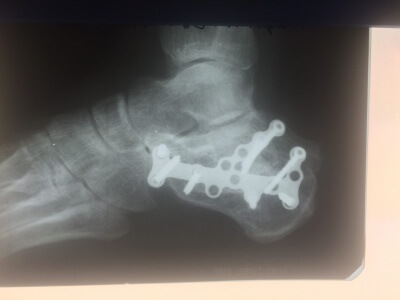

Аугментация костных дефектов дистального отдела большеберцовой кости синтетическим b-трикальций фосфатом и ксенопластическим материалом "Остеоматрикс" при хирургическом лечении внутрисуставных импрессионных переломов

ТРАВМАТОЛОГИЯ